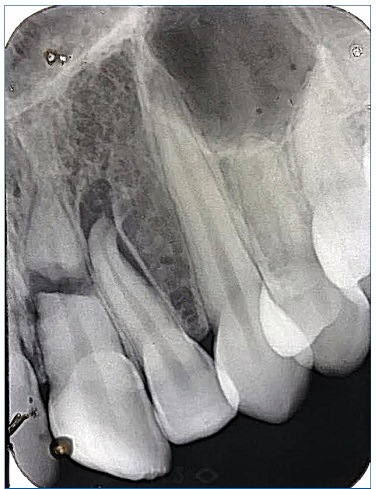

A 15‑year‑old Caucasian female patient was admitted to a private clinic 30 minutes after suffering a severe impact to the oral region during a basketball game at school in 2010. She was not wearing a mouthguard at the moment of the trauma. The intraoral examination revealed a cut on the lower lip and heavy bleeding in the maxilla’s anterior region (Figure 1). Besides, both teeth 21’s (left maxillary central incisor) and 22’s (left maxillary lateral incisor) crowns were slightly dislocated in a palatal and coronal direction, and tooth 21 had an enamel fracture (Figure 2). The patient had vital signs within the normal range and did not have any systemic alterations. Radiographic examination revealed a horizontal root fracture in the middle third of tooth 21 and an enlargement of the periodontal space of tooth 22 (Figure 3). Teeth 21 and 22 did not respond to the cold test with Endo Ice (Maquira, Maringa/PR, Brazil), while the response from teeth 12 (right maxillary lateral incisor), 11 (right maxillary central incisor), and 23 (left maxillary canine) was compatible with a normal pulp. The patient reported pain during the percussion exam on all teeth involved.

Figure 3 Radiographic aspects at the emergency care: root fracture of tooth 21 and tooth 22’s extrusion